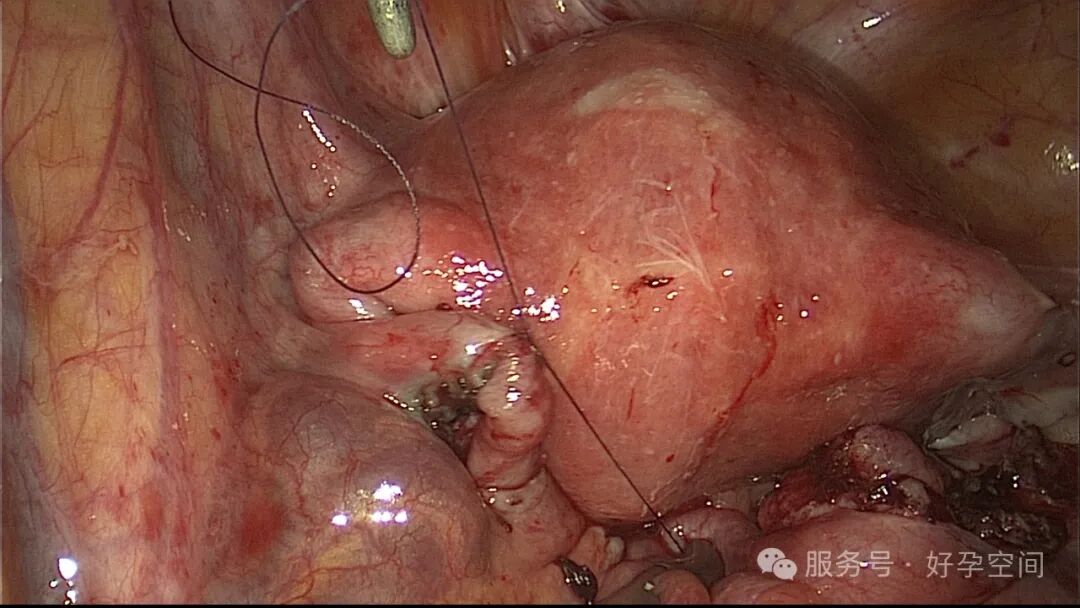

病例3:35岁,原发不孕13年。2020年11月子宫输卵管造影提示左侧输卵管积水,右侧输卵管壶腹部堵塞。2020年12月手术,左侧输卵管伞端造口成形,右侧输卵管壶腹部先天性离断,输尿管导管做支架,行端端吻合术,美蓝通液双侧输卵管均见美蓝液流出。2021年7月自然妊娠,孕17+2周要求引产,住院2天被劝出院,放弃引产。孕17+5周再次住院,坚决要求引产。

1、吻合口大多缝合3~4针,常用4-0或5-0可吸收缝线。文献报道吻合口对合整齐、不旋转、不错位,缝合1~4针均有效,线结打在浆膜面,甚至有不缝合,而用夹子、蛋白胶粘合固定输卵管的报道。缝合是否穿透粘膜层有不同的报道,要完全避免穿透可能难以办到。绝大多数病例都能满足输卵管吻合后长度不短于4cm~6cm。局部注射垂体后叶素不是必须的。

2、术中可以用输卵管支架,对缝合有好处,但不是必须的。支架置入可以通过宫腔镜,或腹腔镜下置入,但均可能失败。输卵管支架可以选择输尿管导管、COOK导管、硬膜外导管等。